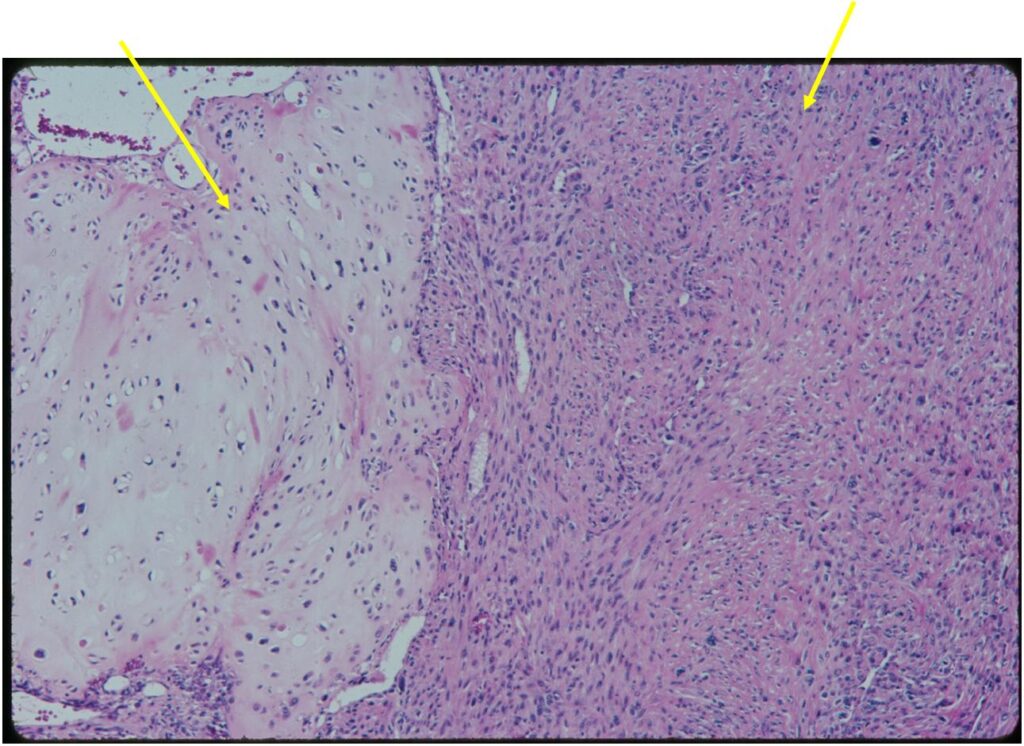

Junction of cartilaginous and noncartilaginous components is sharp and distinct. There are no dedifferentiated areas admixed in the middle of the cartilaginous areas

(Top Arrow) High Grade Dedifferentiated Spindle Cell Sarcoma Component

(Left Arrow) Low Grade Cartilage Component

(Right Arrow) Low Grade Cartilage Component